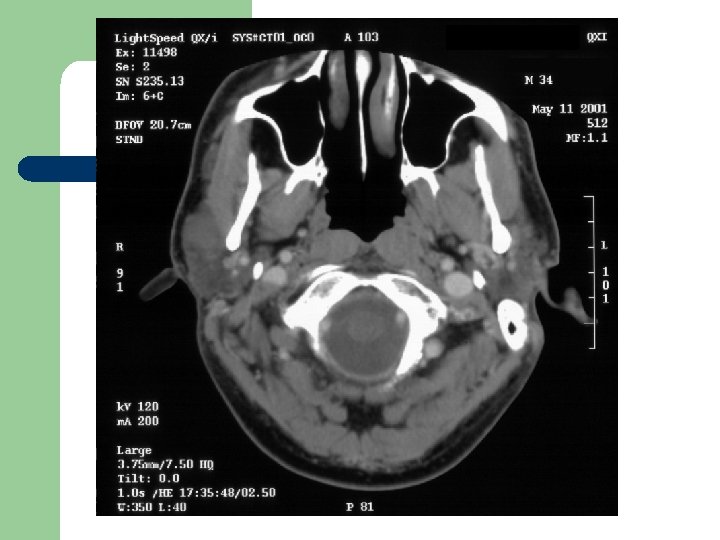

Radiological Evaluation l CT Scan and MRI: To determine the extension of the disease.